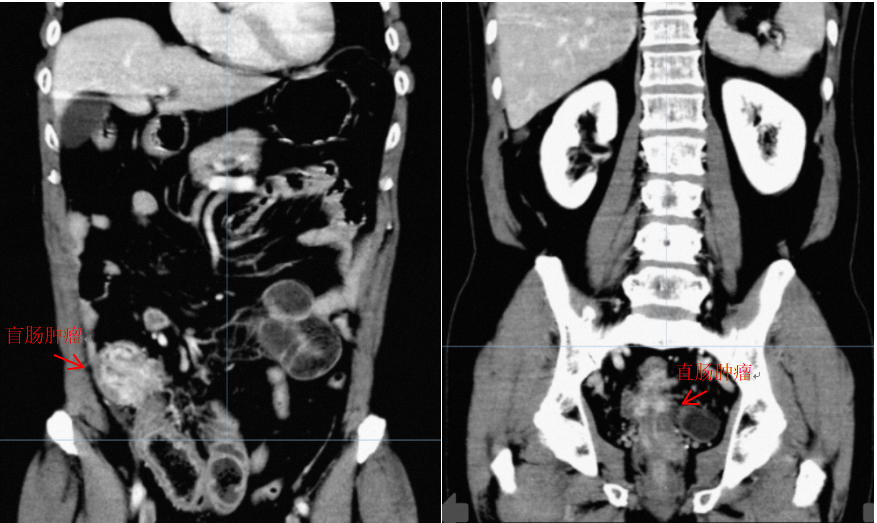

在2022年4月3日施行的腹腔镜探查术中发现,大肠肿瘤分别位于盲肠及直肠中段,均广泛侵犯周围组织器官,且大网膜、腹膜多发种植转移,无法切除,遂予以末端回肠造口解除肠梗阻,并进行腹腔热灌注化疗。

经过9个周期的化疗及5个周期的靶向治疗后,评估盲肠及直肠肿瘤均有不同程度退缩。